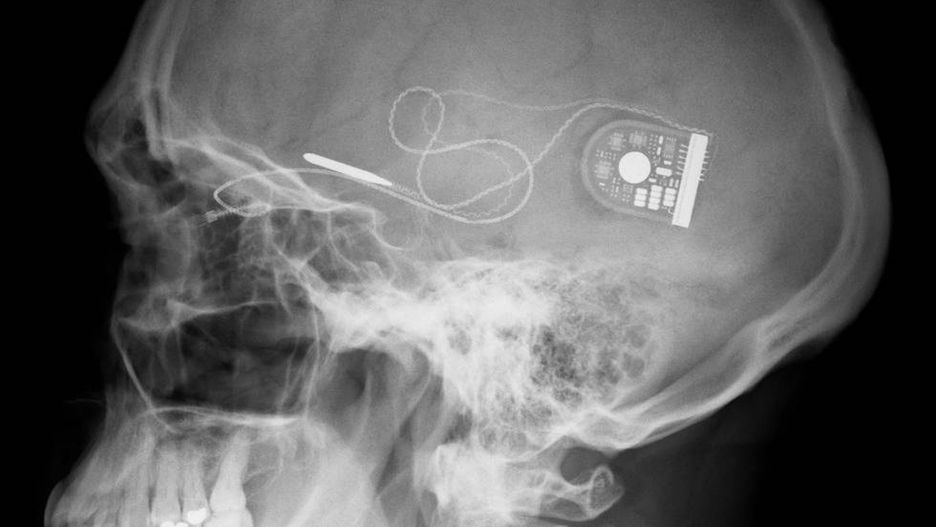

Sposobem na realizację tego celu ma być urządzenie, które dzięki miniaturowym rozmiarom będzie można podpiąć do układu nerwowego. Urządzenie będzie na bieżąco monitorować stan organizmu i zachodzące w nim procesy, a następnie w taki sposób stymulować układ nerwowy, by – np. poprzez zwiększone wydzielanie różnych hormonów - szybciej leczyć różne dolegliwości. Na liście, oprócz przywracania prawidłowej pracy poszczególnych narządów znalazły się m.in. stres pourazowy, padaczka, depresja, choroby zapalne w tym zapalenie stawów.

© Fot. DARPA